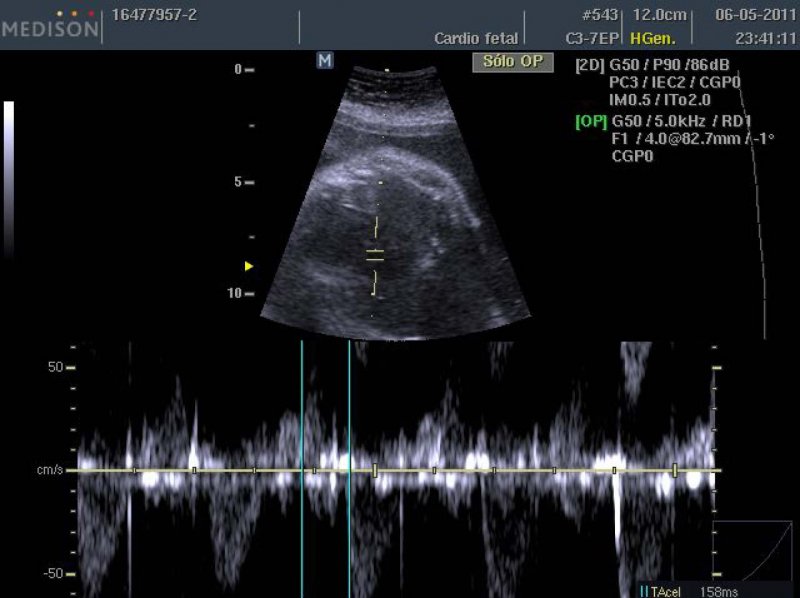

Los exámenes muestran anticuerpos anti-Ro de 37,3 U/ml y anti-La de 6 U/ml, parámetros hematológicos y de función renal normales. Se observa ecográficamente un feto de 1815 g, creciendo en percentil 15 de la curva MINSAL, con Doppler de arteria umbilical y cerebral media normales, y aumento del índice de pulsatilidad (IP >p 95) del ductus venoso. A la exploración cardíaca se observó una prolongación del intervalo PR mecánico (158 mseg) (Figura 1), una leve ecogenicidad en endocardio y válvula mitral, con un aumento del índice de función miocárdica (TEI index de 0,52) sugerente de disfunción ventricular. En el resto de la exploración anatómica destaca polihidroamnios (ILA 25 cm) y una bolsa gástrica pequeña. Los diagnósticos de ingreso fueron BAV de primer grado, miocarditis fetal, probable atresia esofágica con fístula traquoesofágica.

Se inicia tratamiento con dexametasona 4 mg/día, observándose normalización del intervalo PR mecánico al sexto día de tratamiento (Figura 2). Respecto de la evaluación miocárdica, no se observa variación, persistiendo un IP de ductus venoso >p95 y un índice de función miocárdica alterado.

La manera de pesquisar a las pacientes sería mediante la medición del intervalo PR mecánico, definiendo como bloqueo de primer grado a un intervalo PR >150 mseg (17). Esta técnica ha mostrado una buena correlación con el ECG fetal (18). El objetivo de la pesquisa precoz sería iniciar el tratamiento con corticoides, previniendo la progresión a BAVC. Una de las primeras experiencias fue la de Vesel y cols (19), quienes a una paciente con 25 semanas de embarazo, portadora de anticuerpos anti-Ro/anti-La, y en presencia de bloqueo de primer grado, iniciaron dexametasona 4 mg/día por 4 semanas, mostrando regresión de la prolongación del intervalo PR. En un estudio posterior (20), 6 pacientes con BAV de primer grado fueron tratadas con dexametasona, observándose normalización de la conducción AV dentro de 3 a 14 días. Dado el resultado de estos estudios, el tratamiento de los estadios iniciales del BAV con corticoides aparece como una estrategia interesante para prevenir el BAVC en pacientes con anticuerpos anti-Ro/anti-La.